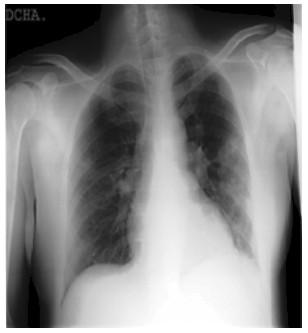

Together with collaborators from Pakistan and Malaysia, a research team from Qatar University in Doha, Qatar, and the University of Dhaka in Bangladesh has created a database of chest X-ray images for COVID-19-positive patients as well as photos of typical and viral pneumonia. This dataset of COVID-19, normal, and other lung infections is being provided in phases. Table 2 shows the details of the COVID-19 Radiography Dataset. Some COVID and Normal patients’ CXR images of this dataset are shown in Figure 3 to Figure 6.

The normal chest X-ray shows clean lungs with no spots of aberrant opacification. Lung opacity is characterized by a localized lobar consolidation, in this case in the right upper lobe (white arrows), whereas viral pneumonia is characterized by a more widespread “interstitial” pattern in both lungs. Pictures that do not meet the aforementioned characteristics are classified as having COVID-19 disease.

Figure 3. Normal CXR image example from the COVID-19 Radiography Database

Figure 4. COVID CXR image example from the COVID-19 Radiography Database

Figure 5. Viral Pneumonia CXR image example from the COVID-19 Radiography Database

Figure 6. Lung Opacity CXR image example from the COVID-19 Radiography Database